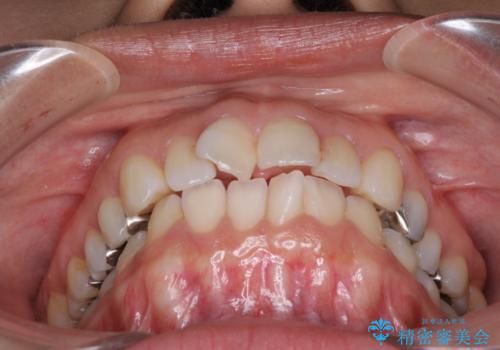

前歯の突出を軽減 インビザラインによる抜歯矯正

- 上の前歯の捻じれと突出感を気にして来院された患者様です。

目立たない装置を希望とのことで、上顎左右第一小臼歯を抜歯し、インビザラインにて矯正治療を行うこととしました。